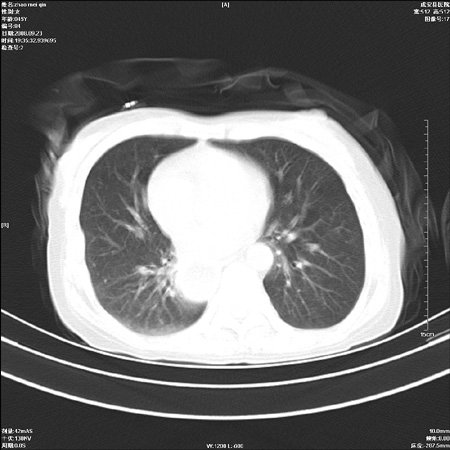

外伤后1小时 胸疼 是外伤后引起的吗?

食道ca术后胸腔胃,右肺挫伤?

非外伤性改变,典型的贲门失迟缓症

食道扩张明显下端逐渐变窄,大量食物存留,象贲门失迟缓症。